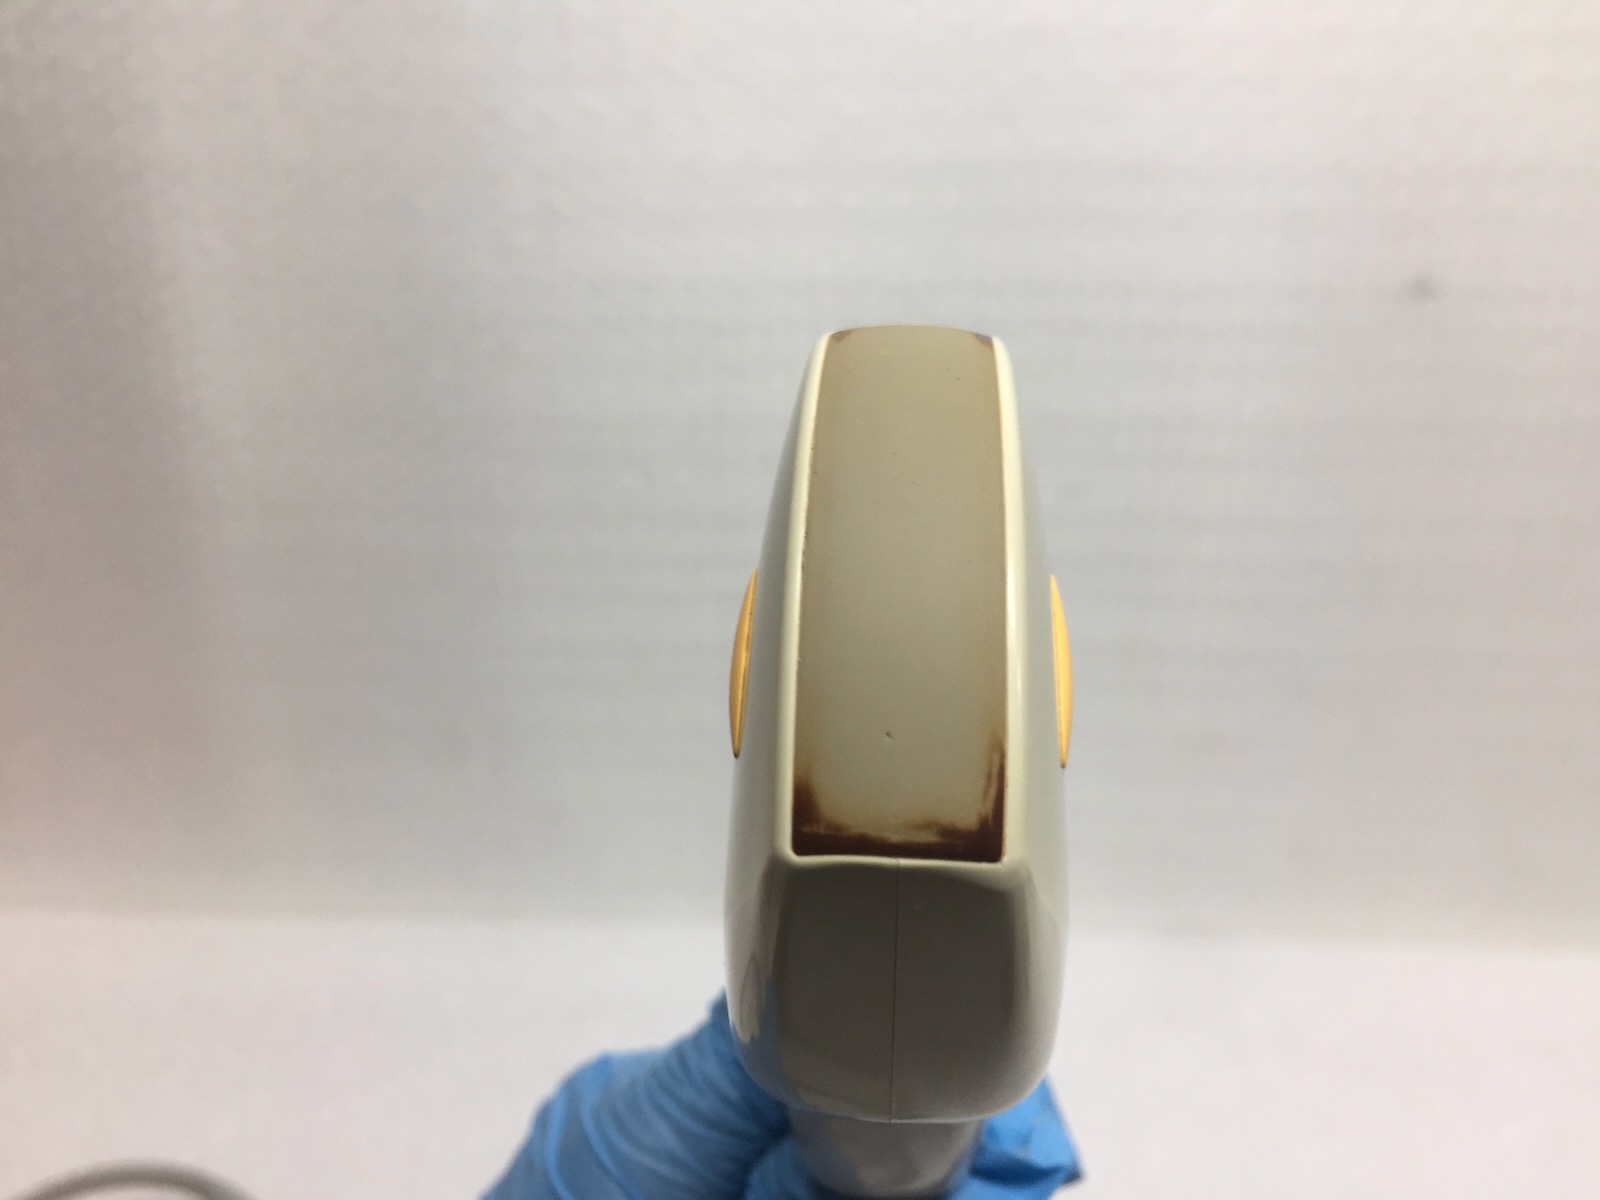

There are a few small blemishes on the membane that are highlighted on the images.